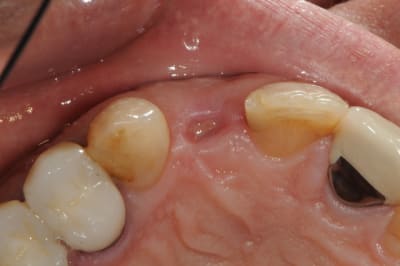

Le cas EII sur 12

positionnement de l'implant en ménageant un espace en vestibulaire qui st comblé avec de l'os synthétique car l'espace est important et il y a une perforation de la corticale vestibulaire en regard de l'apex de la dent.

pour recouvrir tout cela et gagner un peu de volume vestibulaire

un lambeau palatin pédiculé qui après une rotation va recouvrir l'implant et la greffe.

j'ai désépithélialisé la portion que j'ai glissé sous le lambeau vestibulaire, par contre j'ai laissé l'épithélium sur la partie qui recouvre l'implant et qui est "à l'air libre"